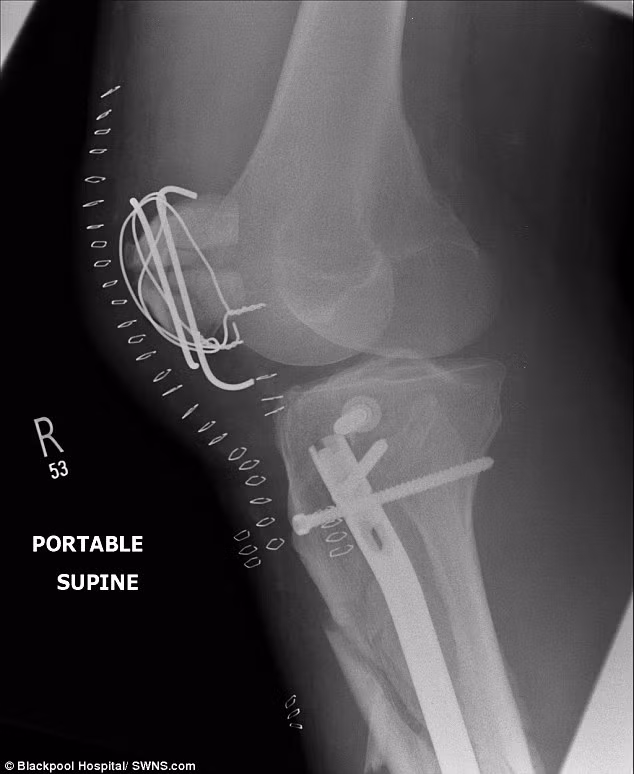

Tổng hợp những chấn thương do tai nạn gồm có: một chân vỡ thành 15 mảnh từ đầu gối trở xuống và cần phải cố định lại bằng đinh vít, nẹp và dây thép; hốc mắt trái bị xê dịch khoảng 2cm, cằm bị vỡ và mũi cũng gần như bị đứt; xương sườn và một số xương trên mặt cũng bị vỡ.

Dù phải mang trên mặt 13 mảnh kim loại và 52 đinh vít nhưng dấu hiệu đáng chú ý duy nhất anh cảm thấy sau khi trải qua cuộc đại phẫu mặt là âm thanh “tích” phát ra mỗi khi anh mở miệng. Tấm phim chụp khuỷu tay được cố định bằng đinh vít, nẹp kim loại và dây thép.